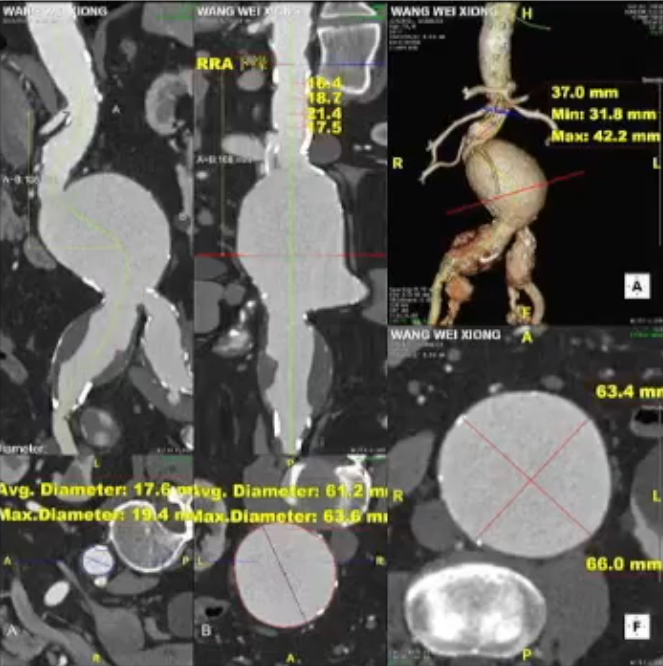

术前情况:74岁男性,肾下腹主动脉瘤,瘤体最大直径66mm,累及双侧髂总,右侧髂内扩张伴开口狭窄,左侧髂内夹层。

术后情况:造影提示动脉瘤完全隔绝,手术成功实现了保留双侧髂内动脉并隔绝动脉瘤的目标,患者病情得到有效控制。

术后造影